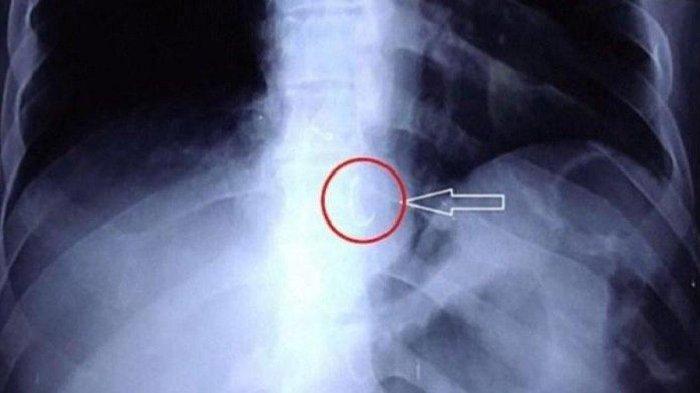

Pasien Syok Gigi Palsunya Hilang Ternyata Tertelan, Nyangkut di Paru-paru, 15 Tahun Kemudian Operasi

Warga Aceh syok mengetahui gigi palsunya yang hilang ternyata tertelan hingga masuk ke paru-parunya.